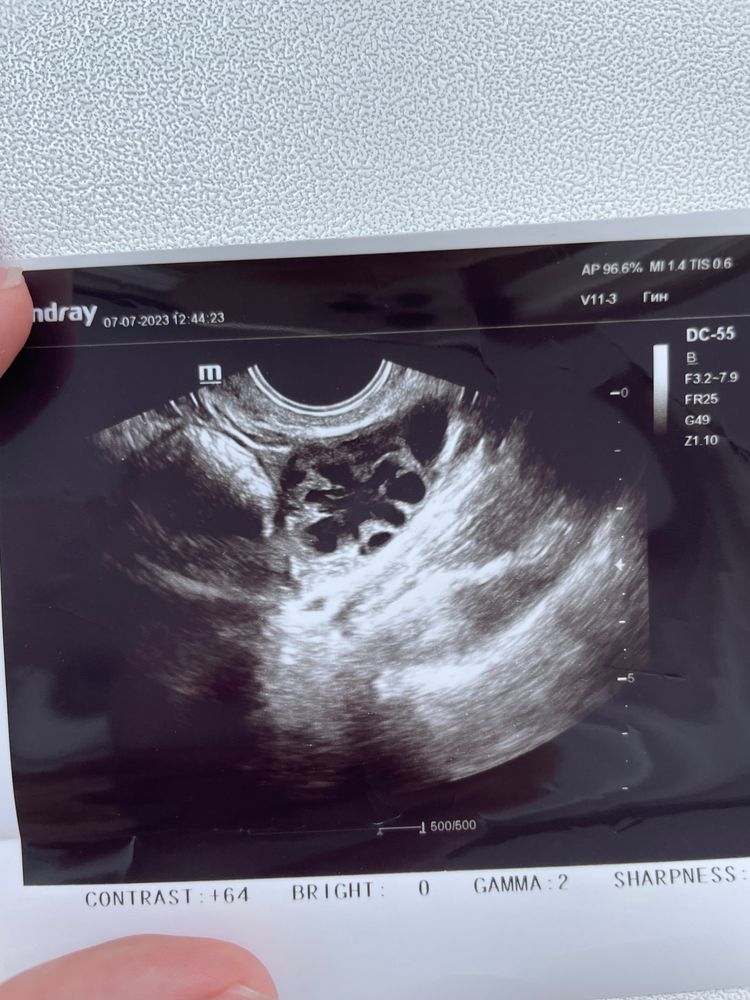

купила хгч укол 10000 ед. сходила к врачу , она мне сказала, будто бы есть желтое тело, и даже без укола хгч… (фото прикладываю, может кто то понимает)

На фото да, жёлтое тело

Екатерина, думаю уже всё, размеры описали? Её видно через несколько дней после овуляции так хорошо